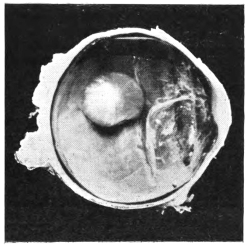

PLATE II.

FACING

PAGE

10.

LENS DISLOCATED BETWEEN CILIARY BODY AND SCLERA

curly bracket span

38

11.

NUCLEUS OF CATARACT FREELY MOVABLE BETWEEN THE AQUEOUS AND VITREOUS CHAMBERS

12.

LENS IMPACTED IN ANGLE OF ANTERIOR CHAMBER

13.

CAPSULE OF MORGAGNIAN CATARACT IMPACTED IN ANGLE OF ANTERIOR CHAMBER

14.

LENS FLOATING FREE IN VITREOUS CHAMBER

15.

LENS LIGHTLY IMPRISONED IN EXUDATE INTO VITREOUS CAVITY